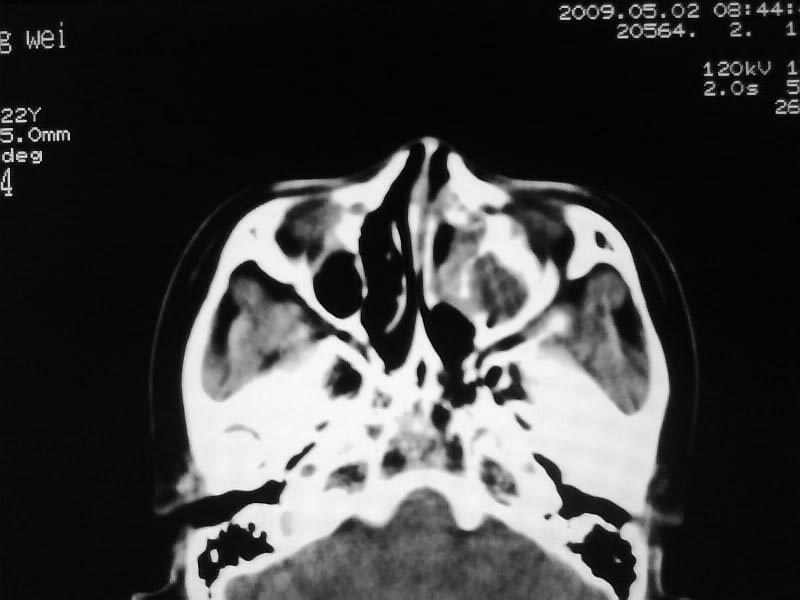

以下是引用zjzjr在2009-5-3 9:59:00的发言:[br]左侧鼻腔息肉、左侧筛窦、上颌窦炎症。双侧下鼻甲粘膜肥厚。

以下是引用随光逐影在2009-5-3 13:02:00的发言:[br]1)左侧鼻腔新生物(息肉可能)。2)左侧上颌窦及左侧筛窦炎症。3)双侧下鼻甲黏膜肥厚。